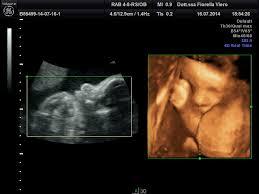

- Ecografia Ostetrica 2D - 3D - 4D